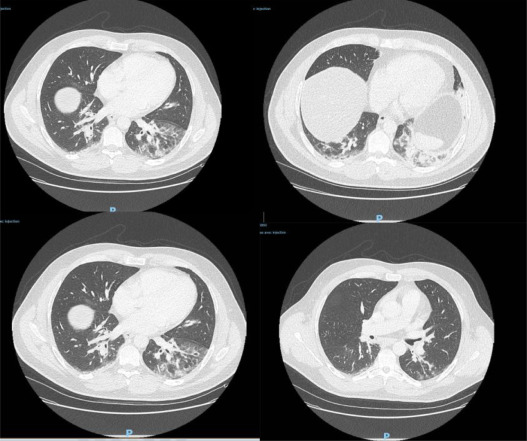

重症监护专家Yves Cohen博士和他的同事们研究了早期患者的记录,寻找是否有未被发现的 COVID-19病例的记录。该团队看了所有12月2日和1月16日之间入院的流感样症状的病例。然后,他们对这些患者的冷冻样本进行了检测,发现有一名男子确实感染了新型冠状病毒。

该男子一直没有来过中国,他的一个孩子也一直在生病。这名男子还患有哮喘和II型糖尿病,在医院住院两天后,经过抗生素治疗,12月29日出院,病情已有好转。然而四天后他的症状加重,因咳嗽伴有咯血、头痛、发热等症状再次进入急诊室。鉴于新冠病毒的症状需要2到14天才能出现,研究人员预计该男子可能是在12月中旬被感染的。